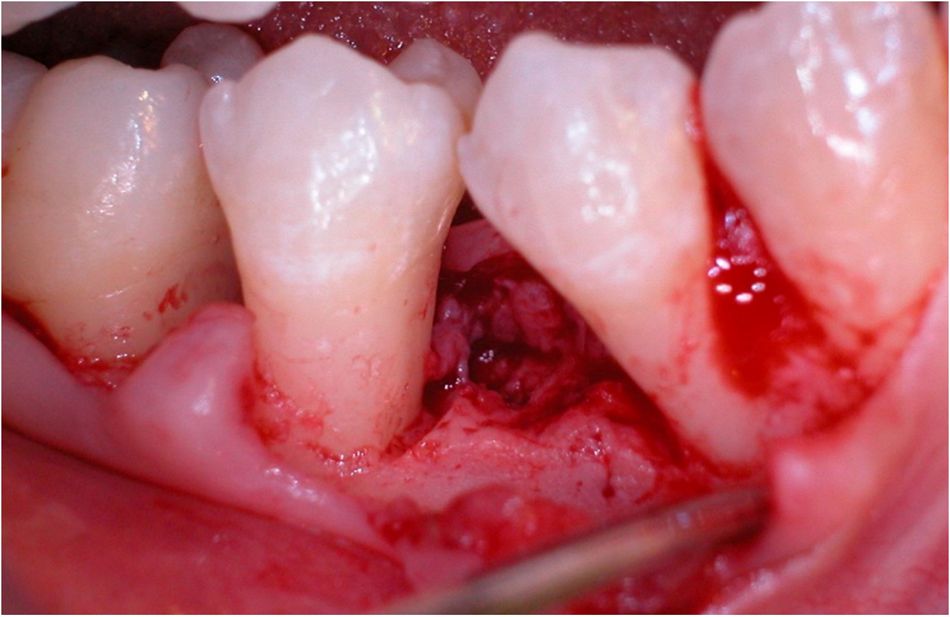

Advanced loss of periodontal support treated with Straumann® Emdogain® – 15-year follow-up clinical case

Straumann® Emdogain® is a unique gel containing enamel matrix derivative of porcine origin. The main component is amelogenin, which has demonstrated the ability to stimulate certain cells types involved in the healing process of soft and hard tissues towards a regenerative pattern, thus leading to true periodontal regeneration1 and accelerated oral wound healing2. Emdogain® has a respected legacy as an irreplaceable tool for periodontology backed by extensive and long-term clinical documentation including studies with 10 years of follow-up3,4. Over the past 25 years it has been used in over 2.5 million patients5 and it is documented in over 1,000 scientific publications, including over 600 clinical papers6 on various indications. For more information: click here.